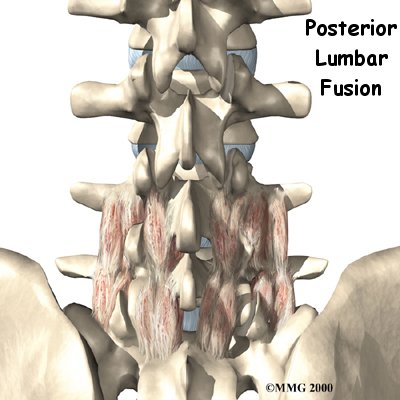

A posterior lumbar fusion is the most common type of fusion surgery for the low back. A fusion is a surgical procedure that joins two or more bones (in this case vertebrae) together into one solid bone. The procedure is called a posterior fusion because the surgeon works on the back, or posterior, of the spine.

Surgeons perform this procedure through an incision in the low back. The incision reaches to the , the bony projections off the back of the vertebrae. The surgeon must move aside the muscles along the spine, called the paraspinal muscles. The fusion itself involves the lamina bone, the protective roof over the back surface of the spinal cord. In some cases, the surgeon may enlarge the neural foramina, the tunnels where the nerve roots leave the spinal cord.

The surgeon first removes any pressure from nearby nerves. This may involve removing part or all of the lamina bone. (The lamina forms the back portion of the bony ring covering the spinal canal.) Then the surgeon takes out any disc fragments and scrapes off nearby bone spurs. In this way, the nerves inside the spinal canal are relieved of additional tension and pressure. The nerve roots are checked to see if they move freely in the spinal canal and as they leave the spine through the small holes between the vertebrae, the neural foramina. If not, the surgeon may cut a larger opening in the neural foramina. This procedure is called foraminotomy.

To prepare the area to be fused, the surgeon shaves a layer of bone off the back surfaces of the spinal column. The cut bone bleeds. The surgeon makes a second incision at the hip. Small strips of bone are removed from the top rim of the pelvis. This is called a bone graft. The surgeon lays the bone strips over the back of the spinal column. When the bone graft contacts the bleeding area, the the bones together just as it would a fractured bone.

During posterior spinal fusion, the surgeon also fixes the bones in place using a combination of metal screws, rods, and plates. This instrumentation (or hardware, as it is sometimes called) holds the vertebrae to be fused together and prevents them from moving. The less motion there is between two bones trying to heal, the higher the chance they will successfully fuse. The use of instrumentation has increased the success rate of spinal fusions considerably.